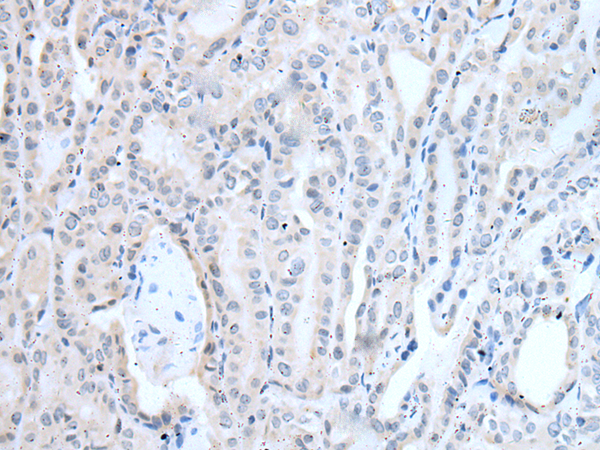

分类: 科研抗体货号: P12761别名: DIRA; IRAP; IL1F3; IL1RA; MVCD4; IL-1RN; IL-1ra; IL-1ra3; ICIL-1RA应用: IHC反应种属: Human